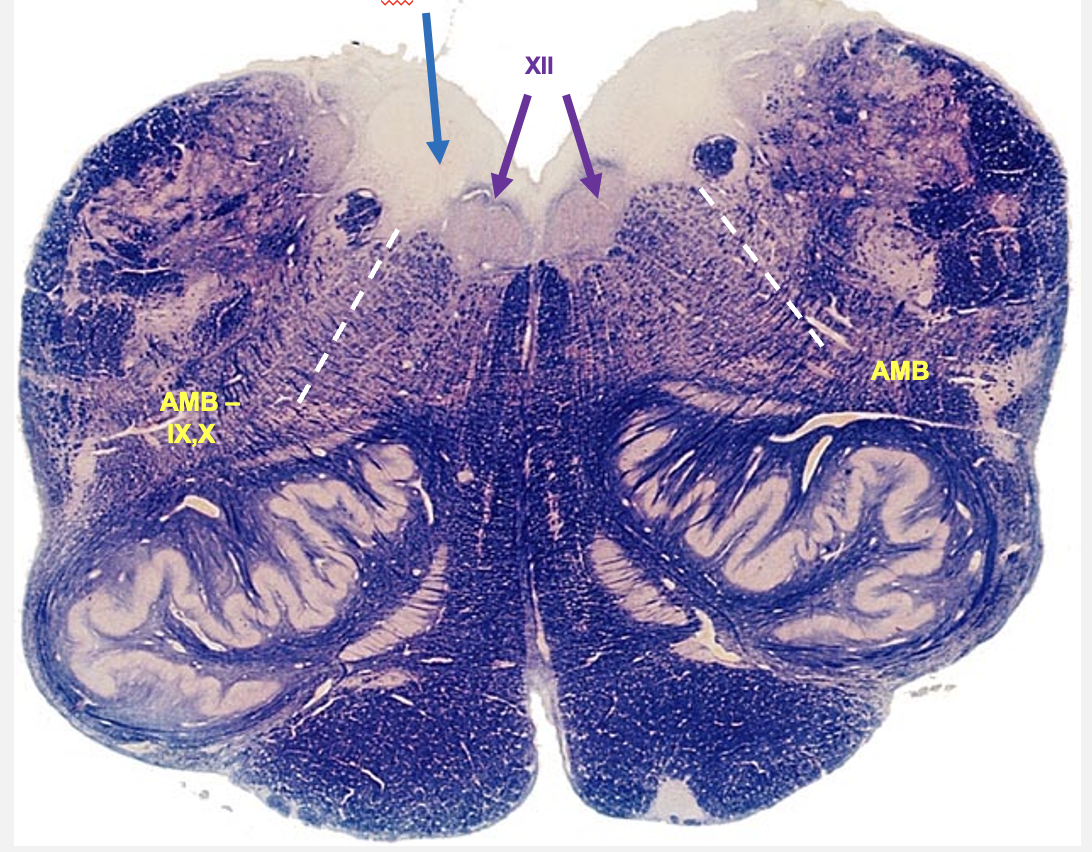

dorsal rostral medulla

fourth ventricle is evident in its cross-section; begin to see the first cranial nerve nuceli at this location

hypoglossal nucleus

dorsal visceral motor vagal nucleus

nucelus ambiguus

nuceli seen on dorsal rostral medulla:

hypoglossol nucleus

nucleus of origin for axons of cranial nerve 12 (somatic motor)

dorsal visceral motor vagal nucelus

contain pre-ganglionic parasympathetic neurons that give rise to axons in cranial nerve 10 that innervate smooth muscle (visceral motor)

nucleus ambiguus

contain neurons that contain axons that innervate larynx and one pharynx muscle (cranial nerves 9 and 10 - branchial motor)